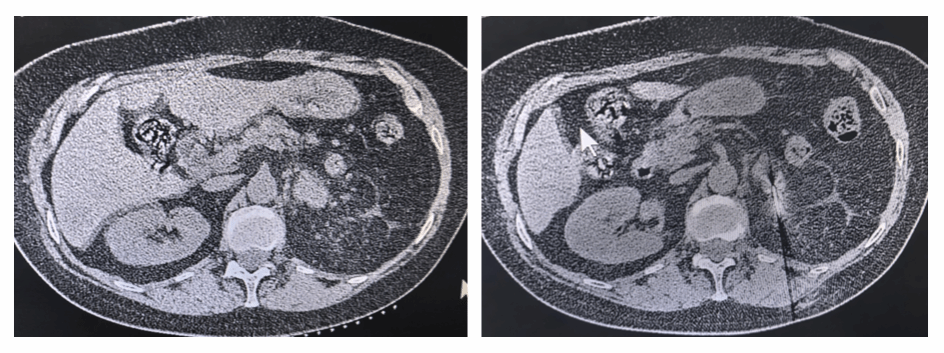

图 2:手术前后肿瘤对比图